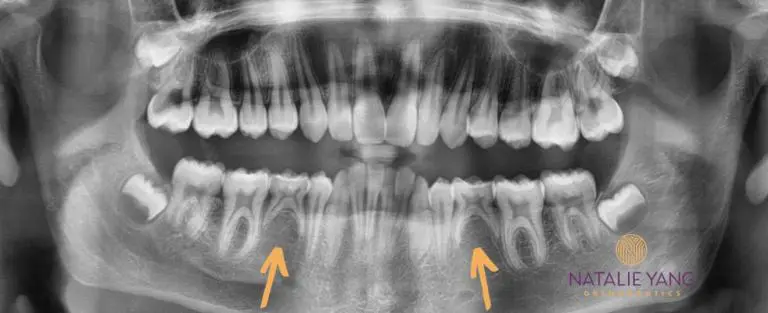

We can spot problems early

In addition to underbites, big overbites, and crossbites, we can also spot problems with the adult teeth inside the jaw bones.

Some common things we look for are:

1. Missing adult teeth – (even with the baby tooth still in place).

2. Adult tooth growing in the wrong direction

3. Adult teeth that are too big for the mouth

4. Adult teeth that are stuck behind other teeth (usually due to overcrowding)

Knowing about these issues early will help you to plan for the future. Sometimes Phase I is necessary for intervention.